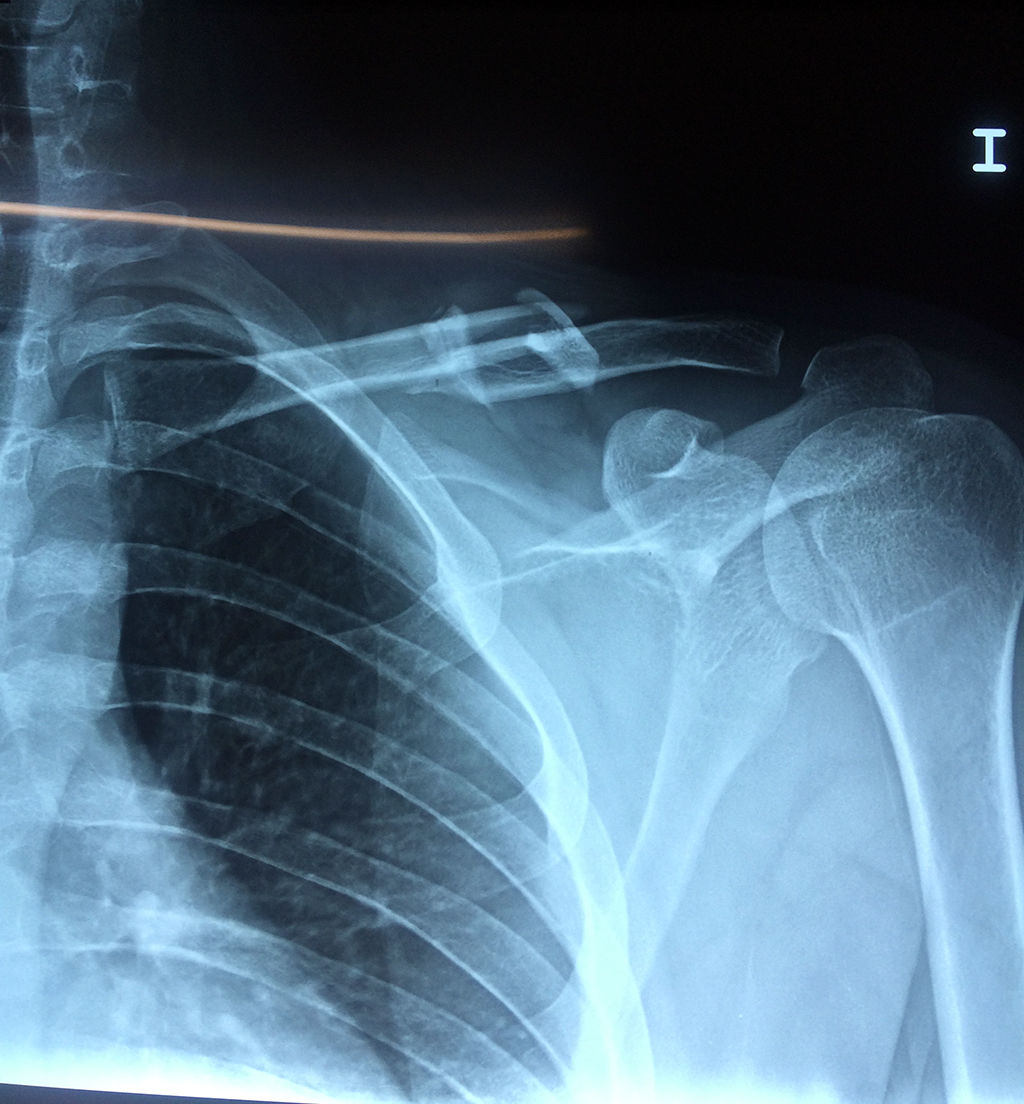

Cirugía de Fémur - Clavícula

La clavícula es un hueso largo, con forma de "S" itálica, situado en la parte anterosuperior del tórax. Junto con la escápula forman la cintura escapular. Se puede palpar por toda su longitud y se extiende del esternón al acromion de la escápula, siguiendo una dirección oblicua lateral y posterior.